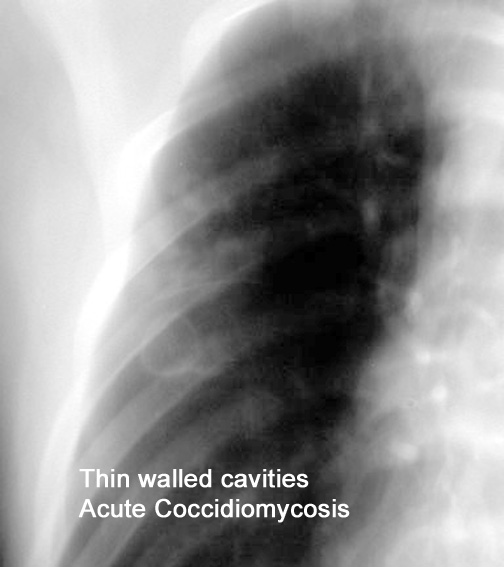

Case 1 Labeled Image What are the conditions where you get thin walled cavities?